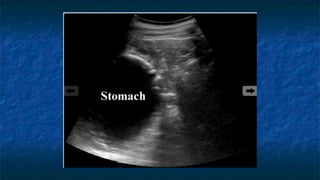

4)FAST: LUQ exam

 Probe placed

 Perpendicular

 Mid - coronal plane

 Just superior to the iliac crest

 Probe facing

 Towards patient’s head

 Evaluating

 Spleno-renal interface

 Possibility of fluid in splenorenal recess

and presplenic /subphrenic space( most

common space for fluid collection in

LUQ)